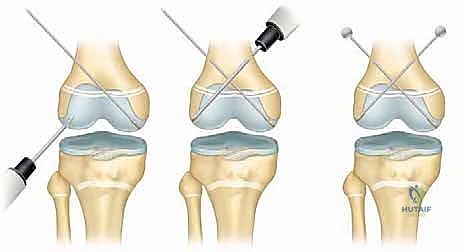

3. التثبيت الداخلي (Internal Fixation)

تتطلب كسور صفيحة النمو أدوات تثبيت خاصة جداً. القاعدة الذهبية في جراحة عظام الأطفال هي: "تجنب اختراق صفيحة النمو بأدوات صلبة قدر الإمكان".

* استخدام أسلاك كيرشنر الملساء (Smooth K-wires): إذا كان لا بد من عبور صفيحة النمو لتثبيت الكسر، يستخدم الدكتور هطيف أسلاكاً معدنية ملساء تماماً (بدون تسنين)، ويتم إدخالها بزوايا متقاطعة دقيقة لضمان الثبات بأقل مساحة اختراق ممكنة، مما يسمح للصفيحة بالاستمرار في النمو.

* استخدام البراغي المجوفة (Cannulated Screws): في كسور (سالتر-هاريس النوع الثاني)، يتم إدخال البراغي عبر "شظية ثورستون-هولاند" العظمية إلى الكردوس، بشكل موازٍ لصفيحة النمو دون لمسها أو اختراقها أبداً. هذه التقنية تتطلب مهارة مكانية (Spatial awareness) عالية جداً يمتلكها الدكتور هطيف.

4. استخدام تقنيات المناظير (Arthroscopy 4K)

في الكسور التي تمتد لداخل المفصل (النوع الثالث والرابع)، قد يستخدم الدكتور هطيف منظار الركبة بدقة 4K لرؤية السطح المفصلي من الداخل والتأكد من تطابقه بنسبة 100%، وإزالة أي شظايا غضروفية حرة قد تعيق حركة الركبة مستقبلاً.